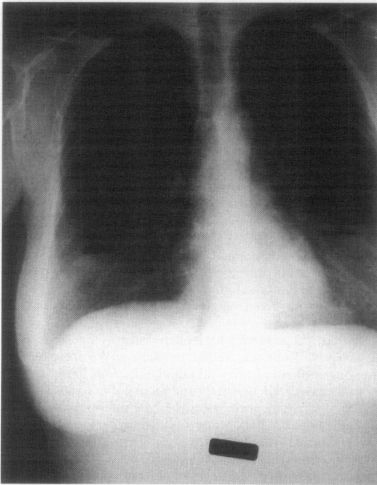

Para o editor: Uma mulher de 51 anos que tinha vindo recentemente do nível do mar apresentou tosse e congestão em nosso pronto-socorro em Frisco, Colorado (altitude, 3.200 m). Ela descreveu um “som de assobio” em seus seios. Ela teve implantes mamários salinos por 20 anos e notou esse som incomum em viagens anteriores a grandes altitudes. Ela disse que o som em seus seios desapareceria em seu retorno ao nível do mar ou desapareciam lentamente durante uma estadia prolongada em grandes altitudes. Uma radiografia de tórax revelou níveis hidroaéreos em forma de crescente em ambos os implantes .

A ar aprisionado em implantes mamários se expande em grandes altitudes de acordo com a lei de Boyle, que afirma que o volume de um gás confinado varia inversamente com a pressão. Aqueles de nós que vivem em grandes altitudes conhecem bem esse fenômeno. Quando voltamos para casa de altitudes mais baixas, nossos tubos de pasta de dente e sacos de batatas fritas se expandem. e assim os implantes mamários.